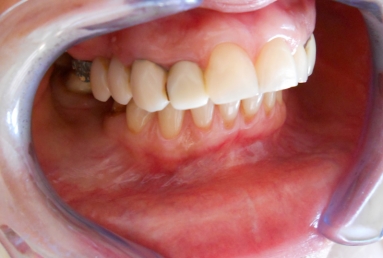

Before treatment: old fractured prosthetic restorations in the lateral maxillary areas made out of metal and composite material, deep bite, frontal maxillary teeth severely inclined.

After treatment:

– zirconium/ceramic bridge in the lateral right maxillary area

– two implants and zirconium/ceramic bridge in the lateral left maxillary area

– full ceramic individual crowns in the frontal maxillary area, correcting at the same time the occlusion and the position of the frontal teeth.

– the lower arch was restored with a zirconium/ceramic bridge in the lateral right area and composite esthetic fillings + teeth whitening for the rest of the natural teeth.